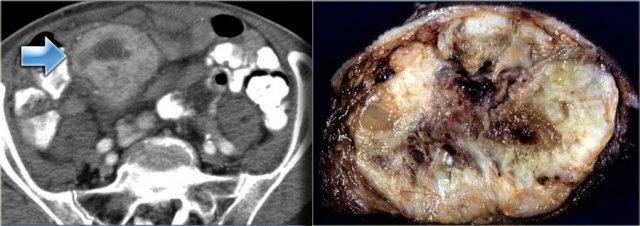

Khối đặc đơn độc này được phát hiện ở vùng chậu.

Dựa trên tiền sử bệnh, tổn thương này được nghi ngờ là di căn.

Các khối u đặc đơn độc khác như … có thể có biểu hiện tương tự.

Cần sinh thiết để xác định chẩn đoán.

Kết quả cho thấy đây là di căn của ung thư biểu mô phổi.